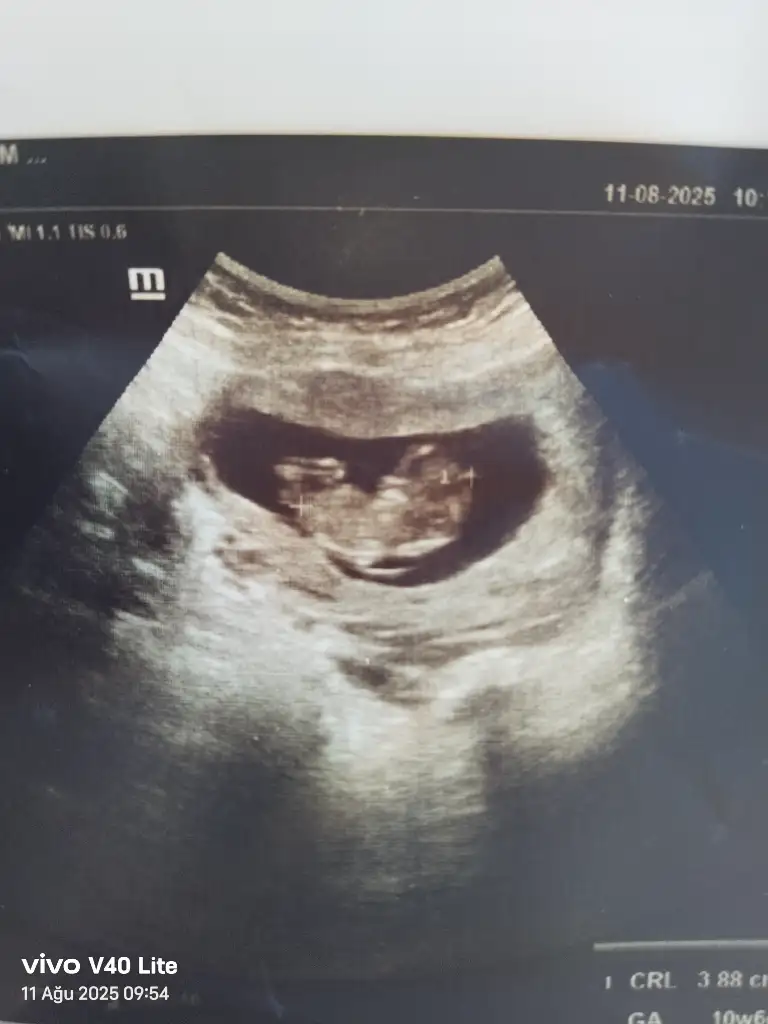

Benim attığımı da tahmin eder mısınız 11+5Bariz erkek görüyorum, sağlıcakla gelsin inşallah![]()

Erkek görüyorum sağlıcakla gelsin inşallahBenim attığımı da tahmin eder mısınız 11+5

Ay erkek demişiim, kız görüyorum olacaktııErkek görüyorum sağlıcakla gelsin inşallah![]()

Ben hep kız hissettim hiç beklemiyordum açıkçası sürpriz oldu bana daAy erkek demişiim, kız görüyorum olacaktıı

İki çizgi olması kız ama nub'u bir tık yukarı doğru erkek mi acaba derken kız yerine erkek yazmışımnub'u dik de olsa o çizgiler birbirinden ayrı olursa %90 kız oluyor